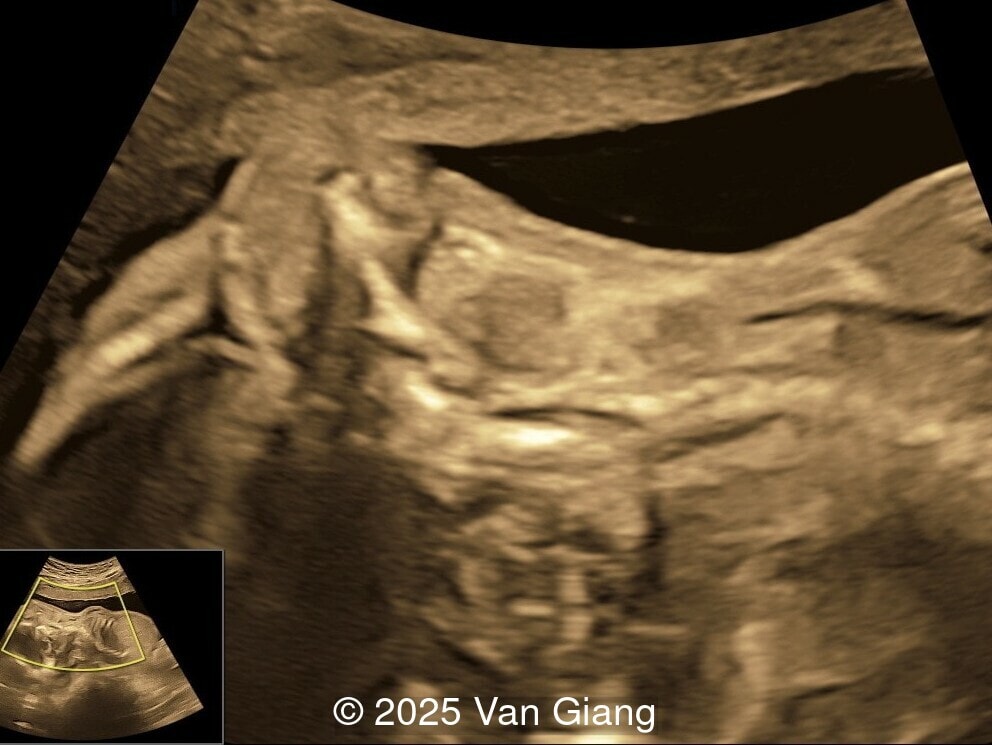

A 32-year-old primigravida presents at 20 weeks gestation without first trimester screening. Ultrasound reveals a small for gestational age fetus with the following anomalies:

Left hand

Image 4 Left hand

Ultrasound revealed severe mandibular and zygomatic hypoplasia, glossoptosis, cleft palate, and micrognathia with an abnormal facial profile. Both upper limbs showed radial ray sequence with abnormal thumbs and shortened forearms. Unilateral clubfoot was also noted. No major cardiac or visceral anomalies were observed. Based on these findings, Nager syndrome was suspected.